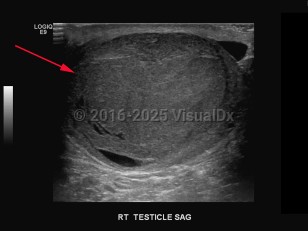

Testicular cancer

A malignant tumor of the testis (one or both), most often of germ cell origin (95%), which may be diagnosed as primary or metastatic cancer. Common presentation includes painless swelling, palpable mass or enlargement in the testis, orchidalgia, fatigue, and infertility. Other symptoms may be flank pain and dull or heavy abdominal sensation. Patients with metastatic disease, depending on the location of the metastasis, may present with gastrointestinal (GI) symptoms (nausea, vomiting, GI hemorrhage, anorexia), edema of extremities, bone pain, back pain, central nervous system abnormalities, cough, dyspnea, or neck mass. Patients with cryptorchidism have greater risk for testicular cancer.